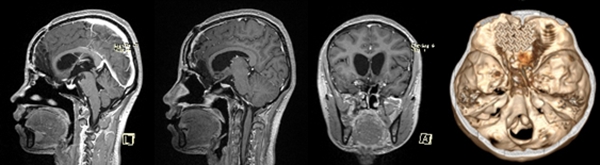

小于術前的磁共振,能夠清晰看到巨大的腫瘤,像豎起的“啞鈴”一樣,連通顱內和鼻腔。重慶醫科大學附屬第二醫院供圖

神經外科主任謝宗義接診后,立即意識到該腫瘤的復雜性和危險性:它像一個巨大的“啞鈴”,一個頭長在顱內,嚴重壓迫腦組織;另一個頭掛在鼻腔,幾乎把鼻腔填滿;中間的連桿則破壞顱底,把顱底骨頭侵蝕出一個大洞,牢牢卡在里面。仔細詢問后,謝宗義得知小于已經出現了頭痛、厭食、視力下降等顱內高壓的危險信號,病情兇險。